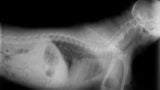

4. 怪我や病気によるもの

呼吸の乱れが長時間続く場合や、他に異常が見られる場合は、怪我や病気が原因の可能性があります。異変を感じたら、早めに動物病院に相談することをお勧めします。